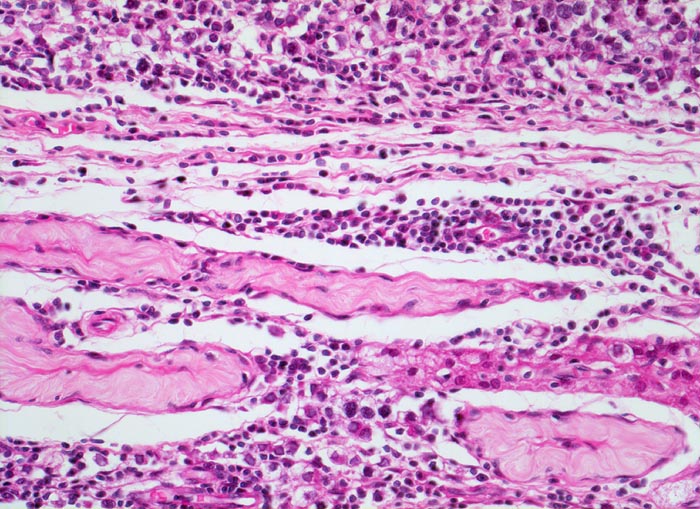

Makroskopisch imponieren Seminome als gut begrenzte weiche crèmefarbene Knoten oder diffuses Intiltrat. Mikroskopisch findet sich eine uniforme Population grosser Zellen mit prominentem zentralem Nukleolus, welche durch schmale Bindegewebssepten voneinander getrennte Nester bilden. Ein leukozytäres Entzündungsinfiltrat, synzytiotrophoblastäre Riesenzellen und Mikroverkalkungen können zusätzlich vorhanden sein. Gelegentlich induziert der Tumor eine ausgeprägte granulomatöse Entzündung. Dies kann zur Fehldiganose einer granulomatösen Orchitis führen.

• Unterschiedlich breite solide Tumorzellstränge aus monomorphen Zellen mit grossen hyperchromatischen Kernen und einem solitären zentralen prominenten Nukleolus. Reichlich helles Zytoplasma mit scharfen Zellgrenzen.

• Schmale bindegewebige Septen mit Kapillaren und lymphoplasmazellulärem Entzündungsinfiltrat.

• Tubuläre Atrophie des angrenzenden Hodenparenchyms. Einige Hodentubuli enthalten stark atypische pleomorphe Keimzellen (Keimzellneoplasie in situ).